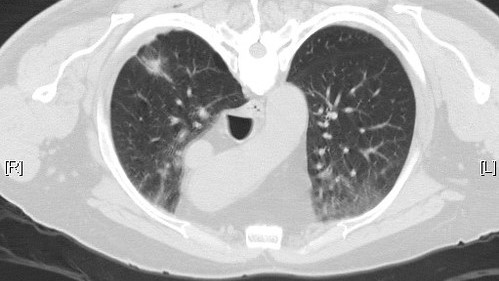

Σε ετήσια εξέταση αξονικής τομογραφίας θώρακα χαμηλής δόσης πρέπει να υποβάλλονται όλοι οι καπνιστές από τα 50 τους και μετά, έστω κι αν έχουν κόψει το τσιγάρο για μια 15ετία.

Ο προσυμπτωματικός έλεγχος του καρκίνου πνεύμονα αφορά όσους έχουν διανύσει τουλάχιστον 20 χρόνια καπνίσματος με ένα ή περισσότερα πακέτα τσιγάρα την ημέρα.

Πρωτογενής και δευτερογενής πρόληψη

«Πέραν της πρωτογενούς πρόληψης που περιλαμβάνει την μη έναρξη του καπνίσματος, ποτέ, στη ζωή ενός ατόμου, η οποία διατυπώνεται συστηματικά και διαχρονικά από τους γιατρούς, η μείωση του κινδύνου για καρκίνο πνεύμονα μπορεί να επιτευχθεί και με αποφυγή έκθεσης σε ραδόνιο ή αμίαντο ή στο παθητικό κάπνισμα, με υγιεινή διατροφή και άσκηση», επεσήμανε ο κ. Κατιρτζόγλου, ενώ συνέχισε αναφερόμενος στη δευτερογενή πρόληψη που αφορά τον προσυμπτωματικό έλεγχο του καρκίνου πνεύμονα (screening), ο οποίος περιλαμβάνει την ετήσια διενέργεια χαμηλής δόσης αξονικής τομογραφίας θώρακα (LowDoseChestCT, LDCT) σε άτομα ηλικίας μεταξύ 50 και 75-80 ετών,που συνεχίζουν να καπνίζουν ή που έχουν ιστορικό καπνίσματος στη ζωή τους τουλάχιστον ίσο με 20 πακέτα-έτη ή άτομα που κάπνιζαν στο παρελθόν και έχουν σταματήσει το κάπνισμα μέσα στα τελευταία 15 έτη, άτομα δηλαδή που θεωρούνται «υψηλού κινδύνου» για καρκίνο πνεύμονα.